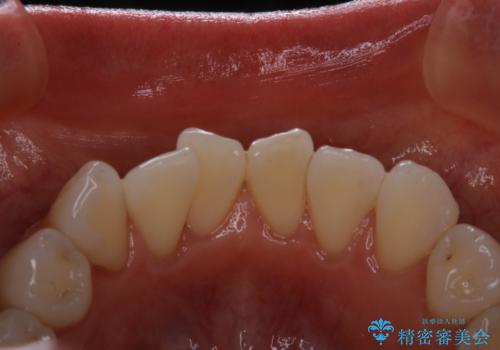

前歯の裏側の着色落としをPMTCでキレイに

- 前歯の裏側だけに着色がついていることが目立つためクリーニングを希望で来院されました。PMTC30分コースを行いました。